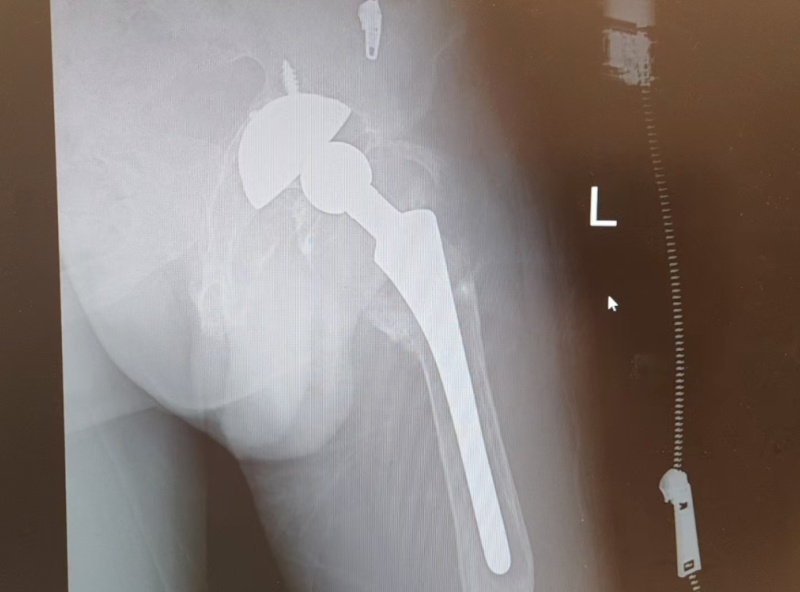

一切准备就绪,关节外科李炜明主任、吴星副主任、李章来副主任、康荣彬主治医师专家团队为陈依伯实施手术。医生切开患处,便看到大量脓液流出来。陈依伯的臀大肌之间还存在大量脓细胞,组织遭受破坏,坐骨神经也被脓液侵蚀,甚至股骨大粗隆及小粗隆的骨质也遭受破坏出现骨折,周围伴有异物巨噬反应。

面对复杂的病情,专家团队凭借精湛的医术和丰富的经验,有条不紊地拔除旧假体,彻底清创不放过任何一处感染,精准装入新假体进行调整。在麻醉科一路保驾护航下,手术历时2个半小时顺利完成。

术后影像